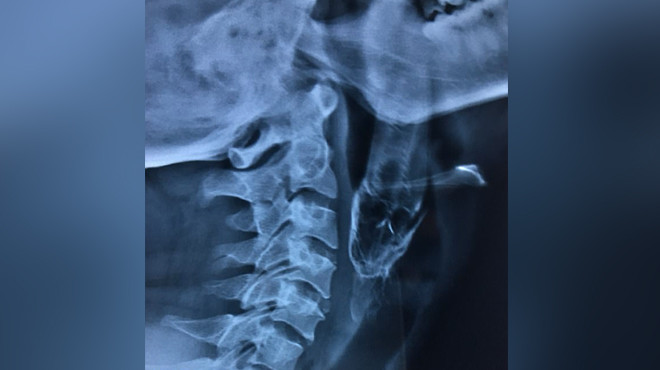

30-летний житель Индии Сантош Даш рыбачил в пруду, когда пойманная им рыба выскочила из рук и попала мужчине прямо в горло, передаёт Daily Mail. Даш с трудом мог дышать и направился в местную больницу, однако там не смогли извлечь существо из его горла.

Мужчину отправили в клинику, которая находится в 200 километрах от его дома. Там Дашу успешно была проведена операция. Для полного восстановления ему десять дней придётся носить трубку.